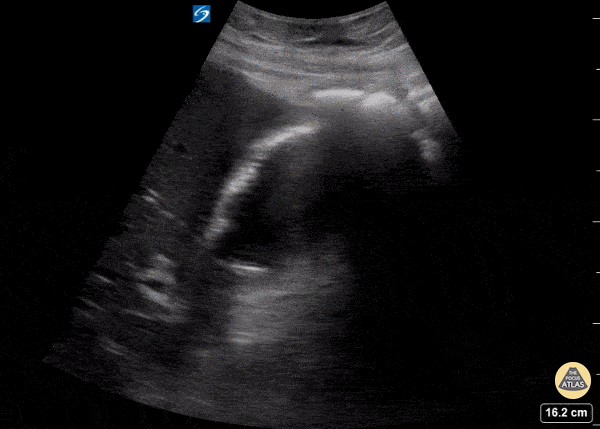

A patient presented with altered mental status and anorexia; clinically he had findings consistent with sepsis. POCUS revealed one angry gallbladder! You can appreciate gallbladder wall thickening (measuring 6mm), trace pericholecystic fluid, and shadowing from gallbladder sludge. Garrett Ghent, Resuscitationst and diagnostician; Norfolk, VA @garrettghentMD